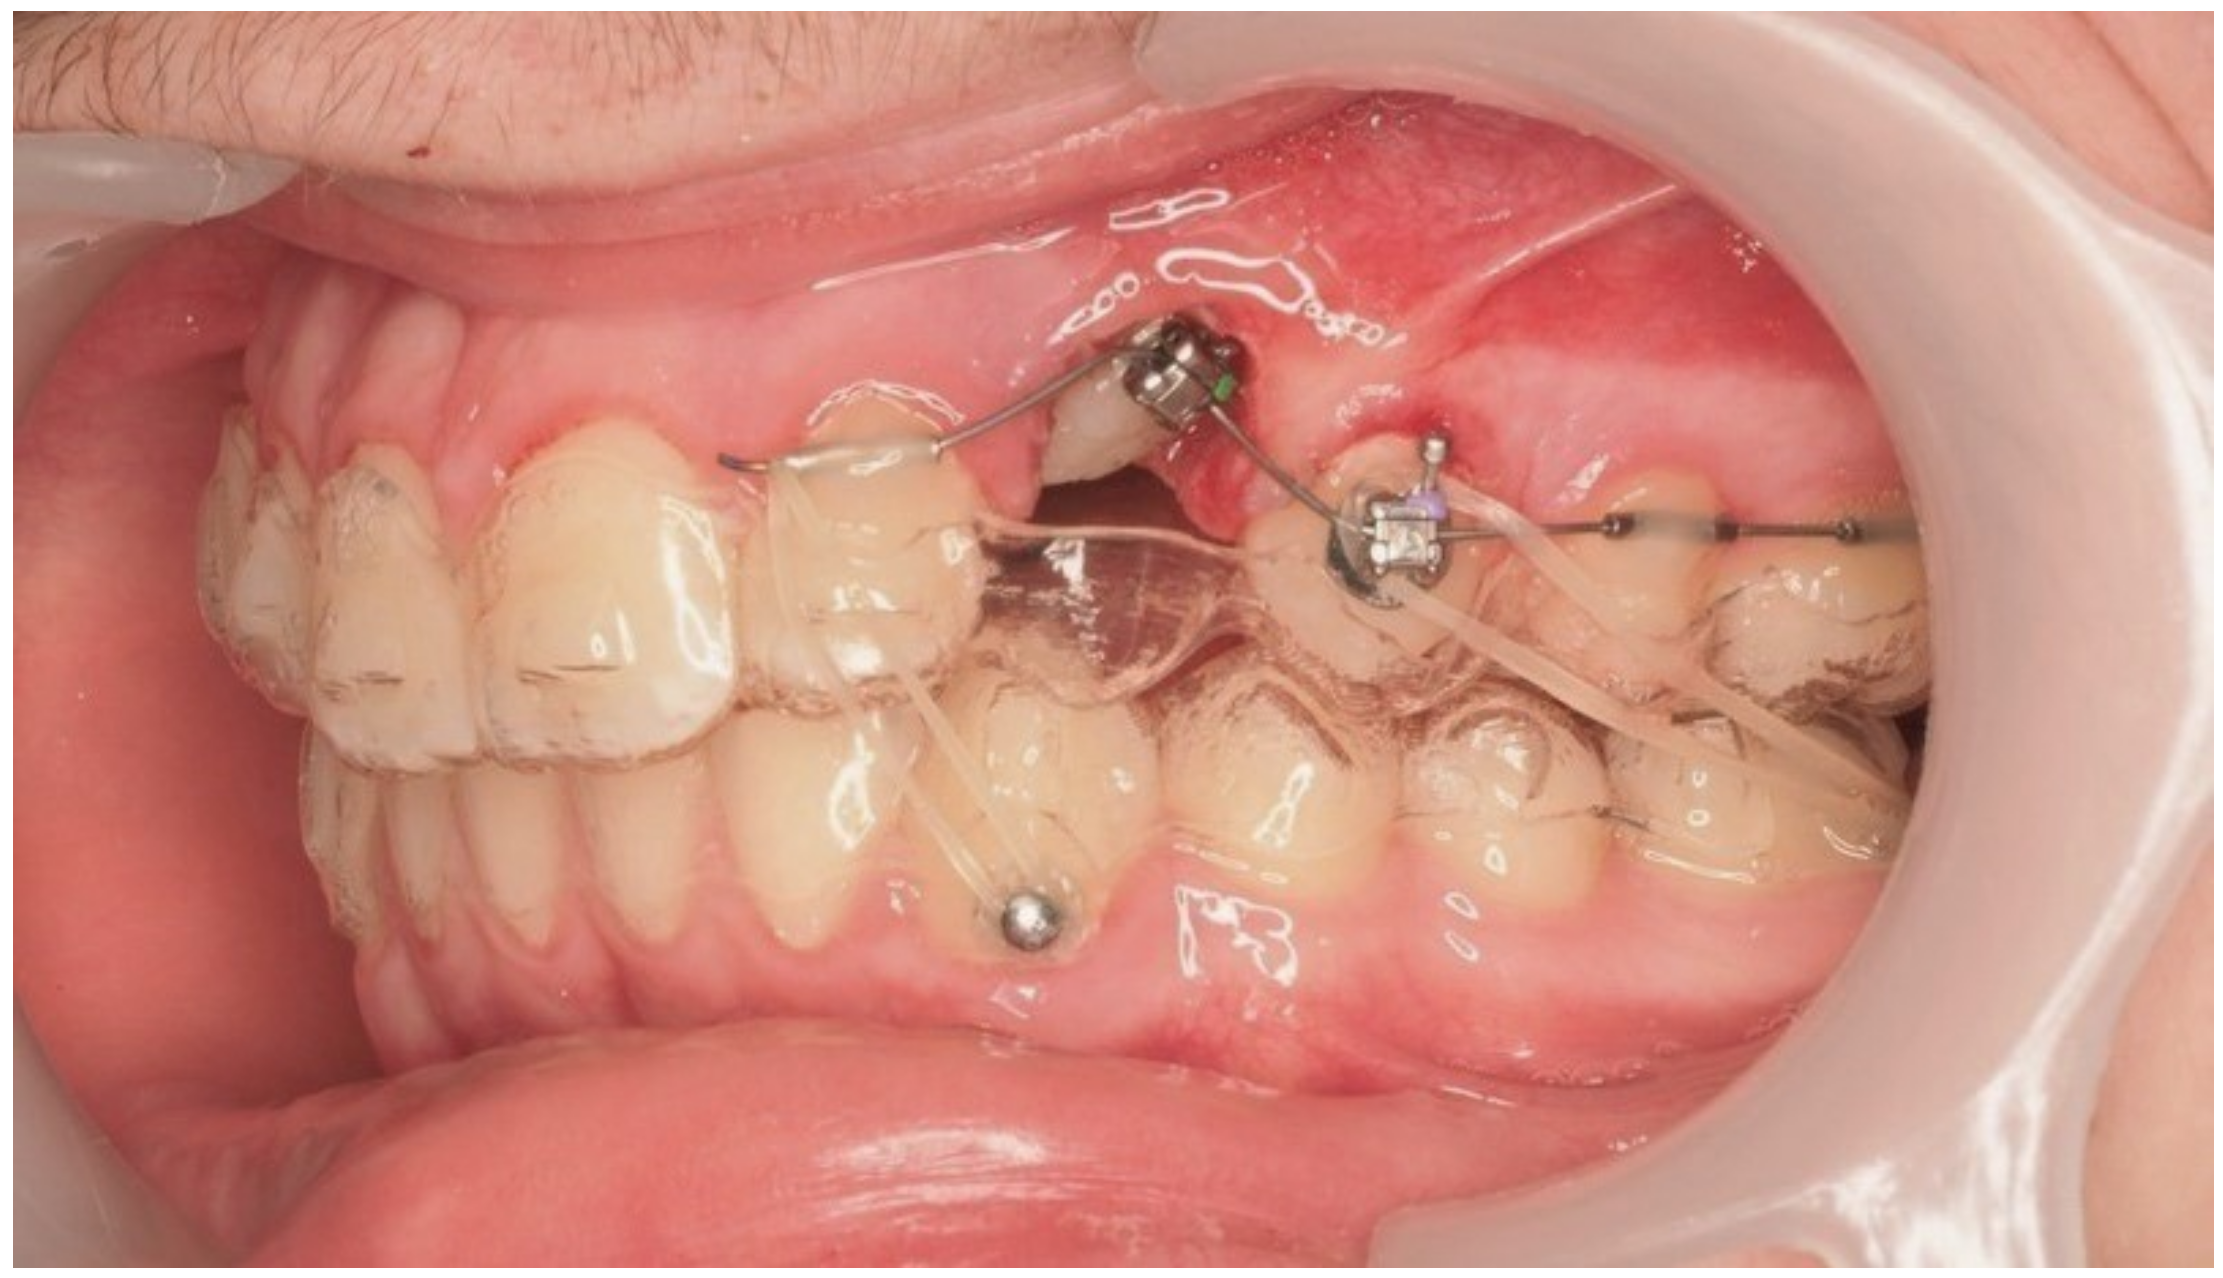

Following initial distalization, a sectional fixed appliance was bonded from tooth 11 to 26. On tooth 24, a bracket with a metallic ligature was used to support Class II elastics. Mini-tubes were bonded on teeth 22, 25, and 26, and the aligners were trimmed accordingly (Figure 16). A ligature wire connected the palatal button on the canine to a 0.014” nitinol archwire (Figure 17).

Figure 16.

Sectional fixed appliance from teeth 11 to 26, with support for Class II elastics to improve sagittal relationship; 14 months after the surgery.

During vestibular traction, gingival removal was required. The canine presented mesial tipping and rotation. In the 14th month after the surgery, a bracket was bonded to tooth 23, following its inclination. A button was bonded on tooth 33 and connected by elastic to tooth 22 to stabilize the vertical position. Another elastic with a Class II vector was attached from the bracket on tooth 24 to a precision cut in the lower aligner (Figure 18).

Figure 18.

Vestibular traction of the canine, gingival removal, and elastic use for vertical stabilization; 14 months after the surgery.